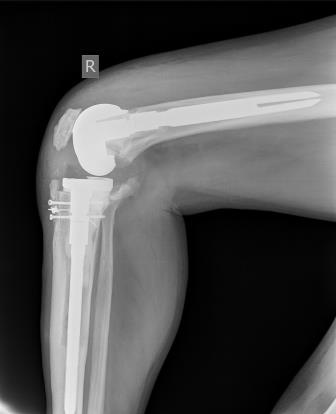

Rezidive der tiefen Patellae kommen trotz korrekter Wiederherstellung der „Joint-Line" immer wieder vor, sodass ein alleiniger TP-Wechsel oft nicht ausreicht und eine Kombination mit anderen Methoden angewendet werden muss, um ein zufriedenstellendes Resultat erzielen zu können (siehe Abb. ).